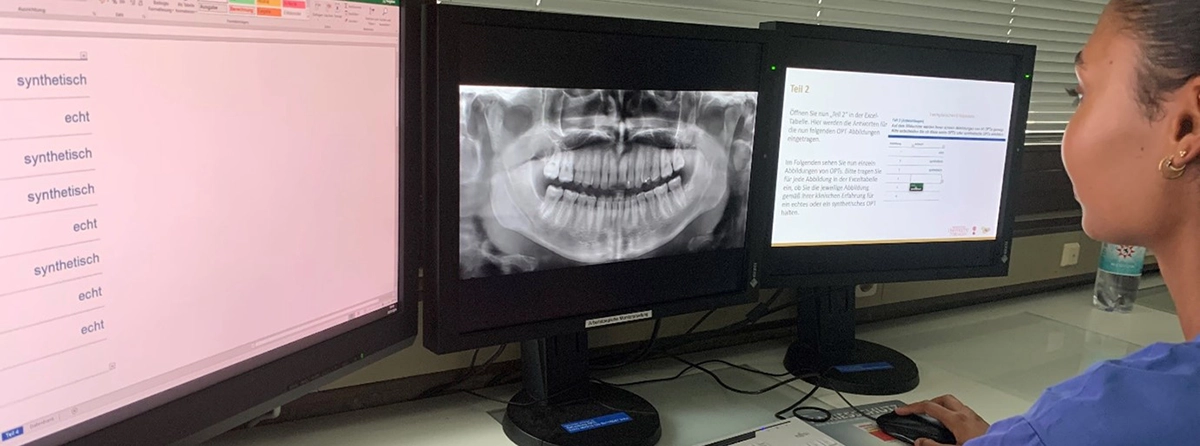

In einem umfangreichen, randomisierten, verblindeten Fragebogen wurden 54 approbierte (Zahn-)Ärzt/-innen und 33 Zahnmedizinstudierende gebeten, die Authentizität der Bilder zu prüfen, indem sie die o.g. 45 Bilder entweder als real oder synthetisch bewerteten (Abb. 1 und 2). Zusätzlich wurde ein Einzel-syOPG hinsichtlich spezifischer, diagnostischer Kriterien befundet (Abb. 3). Ferner wurde nach der Selbsteinschätzung sowie der Einschätzung der Bedeutung von synthetischen radiologischen Bildern für den Beruf gefragt. Ein Follow-up-Test zur Überprüfung der Reliabilität wurde ebenfalls durchgeführt.